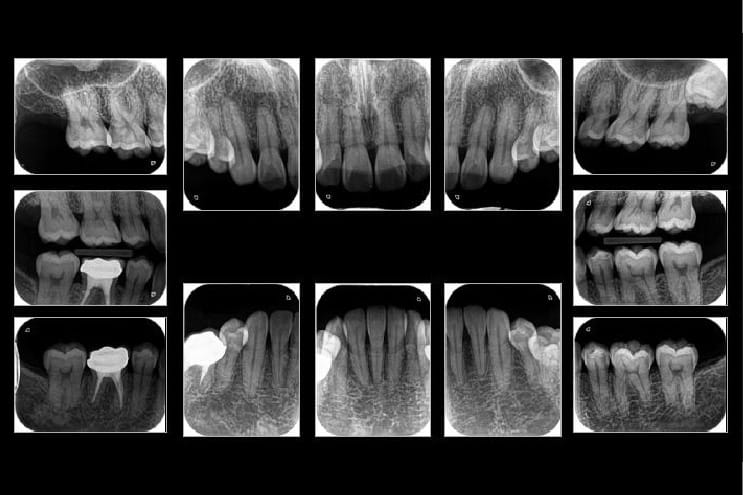

• ■レントゲン

レントゲンも規格性を重視し、1本1本の歯の状態を確認をするために撮影を行います。

すぐに治療が必要な歯があった場合には、応急処置をさせていただきます。

レントゲン